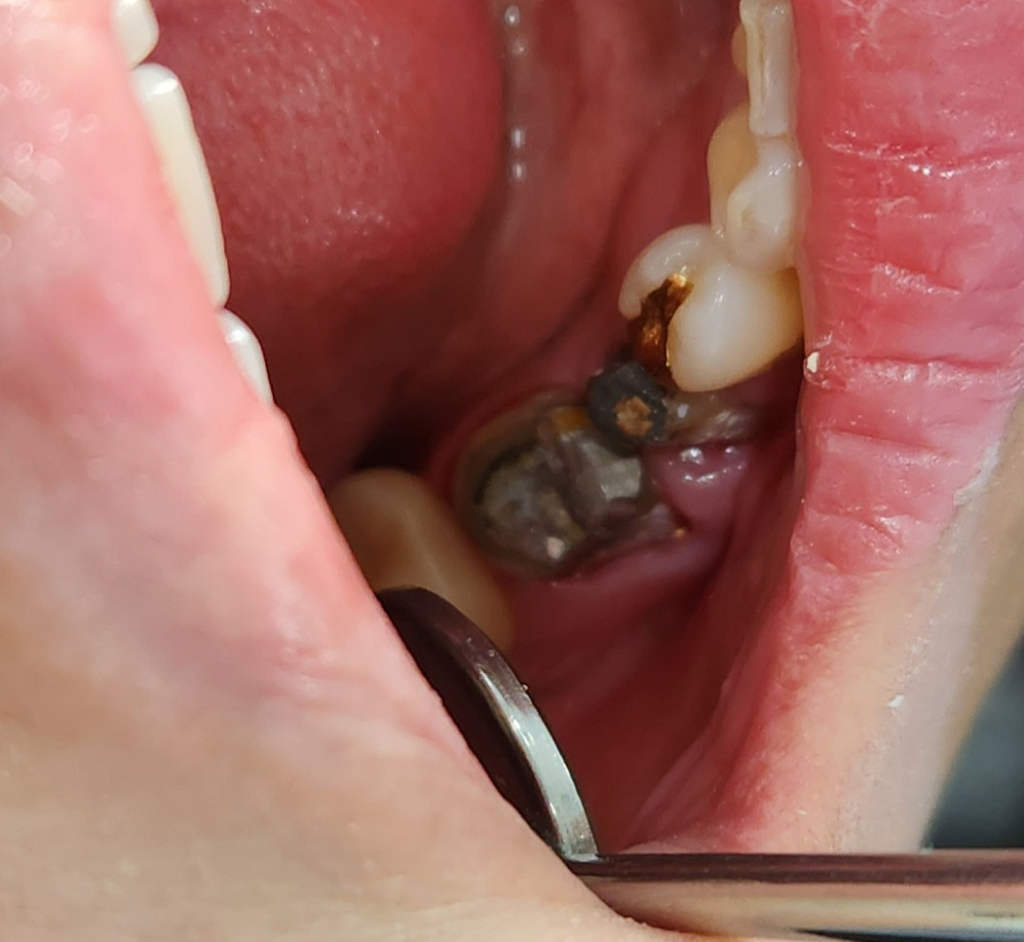

오래된 크라운 재치료중인데 잇몸도 부어있고 뿌리염증도 보이는데 충치제거 하고 크라운 그냥 씌워도 될까요?염증이 있고 잇몸도 좀 부어있어서 걱정인데 재신경치료나 이런치료는 안하고 있다고 하네요 (대형 체인치과) 병원마다 스타일이 있다나요? (치과상담사가 그렇게 이야기함) 다른병원에서 재신경치료하고 와도 된다고..아니면 20만원 제하고 환불을 해준다고 하는데 충치 치료하고 레진코어 충전해서 그렇다고 하네요..사실상 치료는 끝났고 크라운 부착만 남겨놓은 상태에서 어떡하면 좋을지 현명한 답변 부탁드려요 (끝에서 두번째,세번째 아래어금니)

현재 상태에서는 이대로 씌우게 되면 증상이 멈추지 않습니다. 재신경치료를 꺼려하는 것은 대부분 실패할 가능성이 높기 때문입니다. 재 신경치료를 실패하면 그 다음은 발치 이후 임플란트나 브릿지 밖에 없습니다. 하지만 지금 상태에서는 이대로 씌우는 것은 의료가 아니며 이는 환자의 불편감만 커질 뿐입니다. 가급적이면 치료를 하시길 바랍니다.

사진으로만 봤을 경우에는 #46 치아 뿌리끝에 약간의 염증이 보이고 있습니다.

잇몸이 내려간것은 크게 문제가 되지는 않을것으로 보이나 뿌리끝의 염증으로 인해서 생기는 통증이라면 재신경치료가 필요할수 있습니다.

일반병원에서는 재신경치료를 잘 하지 않습니다. 성공률이 높지 않기 때문입니다. 뿌리끝에 약간의 염증이 보이고 잇몸이 부워잇는 상태이신거 같은데 잇몸치료를 조금더 받아보시고 크라운치료를 마무리 하시는게 어떠실지요.